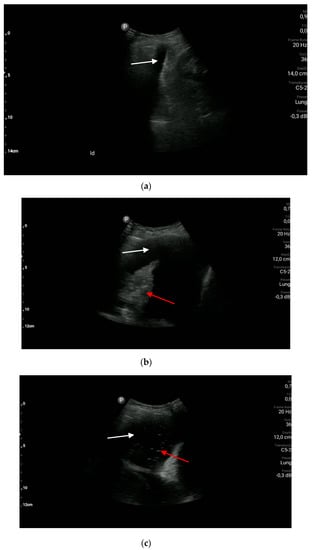

3.1.1. Pneumothorax

- The sonographic features of pneumothorax are as follows: absence of lung sliding, absence of vertical reverberation artifacts, absence of the lung pulse sign, and the presence of the lung point. (A1)

- The presence of lung sliding and/or vertical reverberation artifacts rising from the pleural line and/or the lung pulse excludes pneumothorax. (A1)

- In a patient with acute respiratory failure and with a significant suspicion of pneumothorax, it is not necessary to search for the lung point. (A1)

- Lung ultrasound is a superior diagnostic imaging technique to chest X-ray for patients with pneumothorax; however, lung ultrasound is less useful than chest X-ray for making therapeutic decisions, such as chest drainage. (A1)

- Convex and linear transducers are recommended for the diagnosis of pneumothorax. (A1)

- (a)

- The absence of the lung point with the simultaneous presence of pneumothorax occurs in cases of critical or mantle pneumothorax.

- (b)

- Prior pleurodesis affects the presence of lung sliding (the sign will be absent or limited) and of vertical reverberation artifacts (artifacts emerge due to pleural line abnormalities). The presence of vertical artifacts excludes pneumothorax in patients who underwent pleurodesis.

- (c)

- Loculated pneumothorax—a pocket of pleural air can be visualized; the air in the pleural cavity does not move with the change of the patient’s position.

- (d)

- The lung point is the border between the pocket of pleural air and the normal pleural cavity; this sign can be visualized in the B or M-mode.

- (e)

- The lung pulse is the pulse of the lung resulting from cardiac motion transferred to the lung; the lung pulse is best visualized in the M-mode and/or power/color Doppler options.

- (f)

- The recommended position during the examination is the supine position (except for patients with orthopnea).